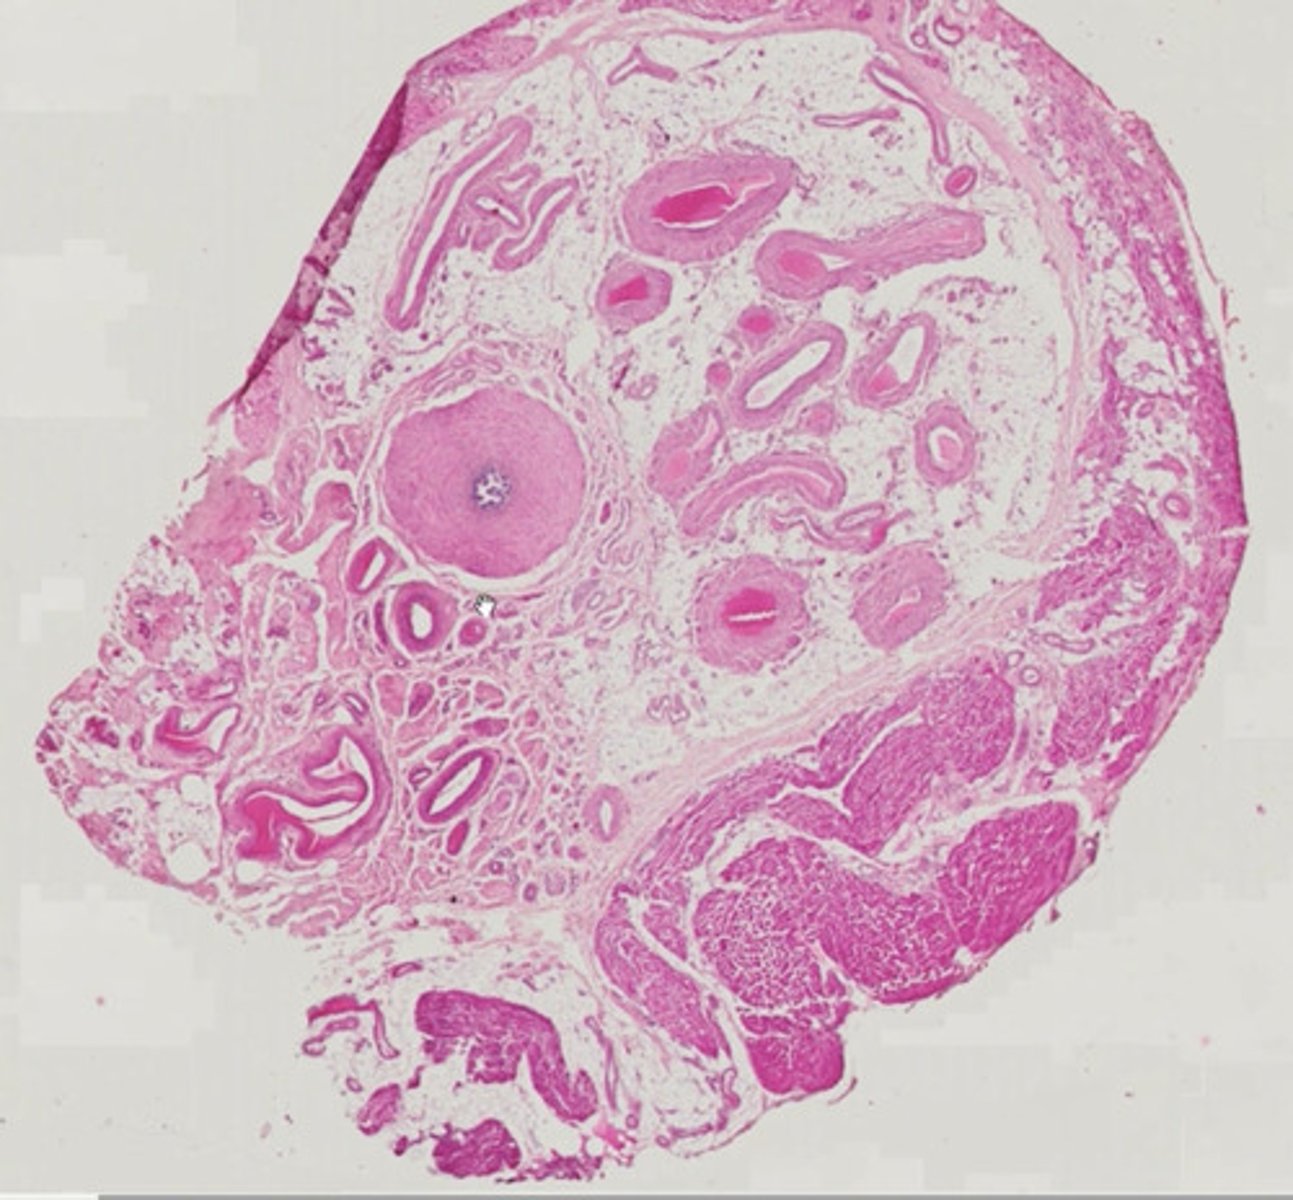

Jajnik (H+E)